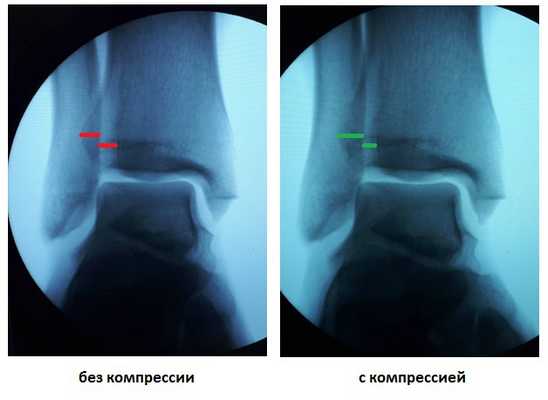

При выполнении стресс рентгенограмм определяется выраженная латеральная нестабильность голеностопного сустава.

У данного пациента также определялась избыточная подвижность малоберцовой кости на уровне дистального межберцового синдесмоза при компрессии голени на уровне средней трети, которая клинически проявляется болью по переднему краю наружной лодыжки.

После восстановления латерального связочного комплекса по Брострому в модификации Голда и фиксации межберцового синдесмоза винтом производится оценка стабильности голеностопного сустава при помощи вальгус—стресс теста под контролем ЭОП.

Гипермобильность голеностопного сустава устранена, положение таранной кости остаётся неизменным несмотря на приложение вальгусной нагрузки.